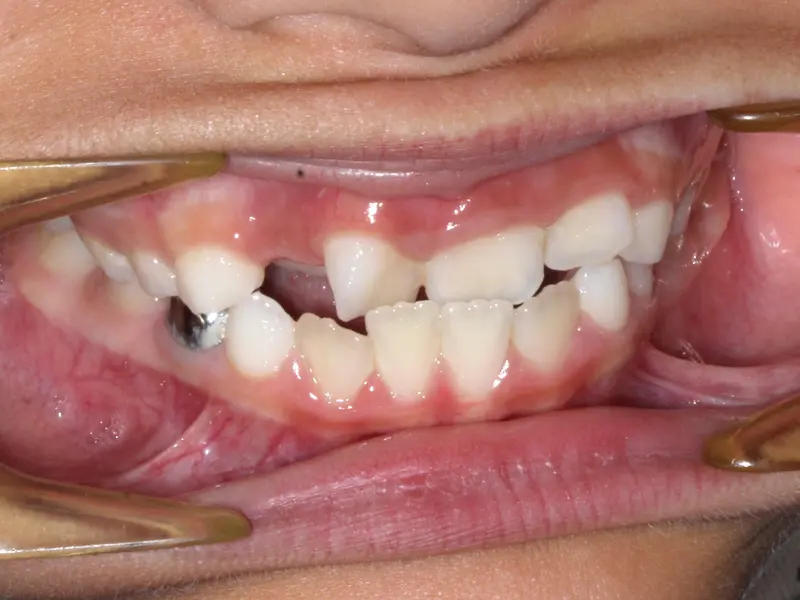

The Diagnosis

Deep bite with over-erupted upper central incisors. The patient presented with a "Gummy Smile" and uneven gingival margins, where the front teeth sat too low relative to the upper lip.

The Engineering

We utilized Temporary Anchorage Devices (TADs) to apply pure intrusive forces. By anchoring to the bone, we lifted the anterior teeth and gum line upwards (Intrusion) to reduce the gummy display and level the smile arc without jaw surgery.

Before treatment: Vertical Control & Intrusion

Before